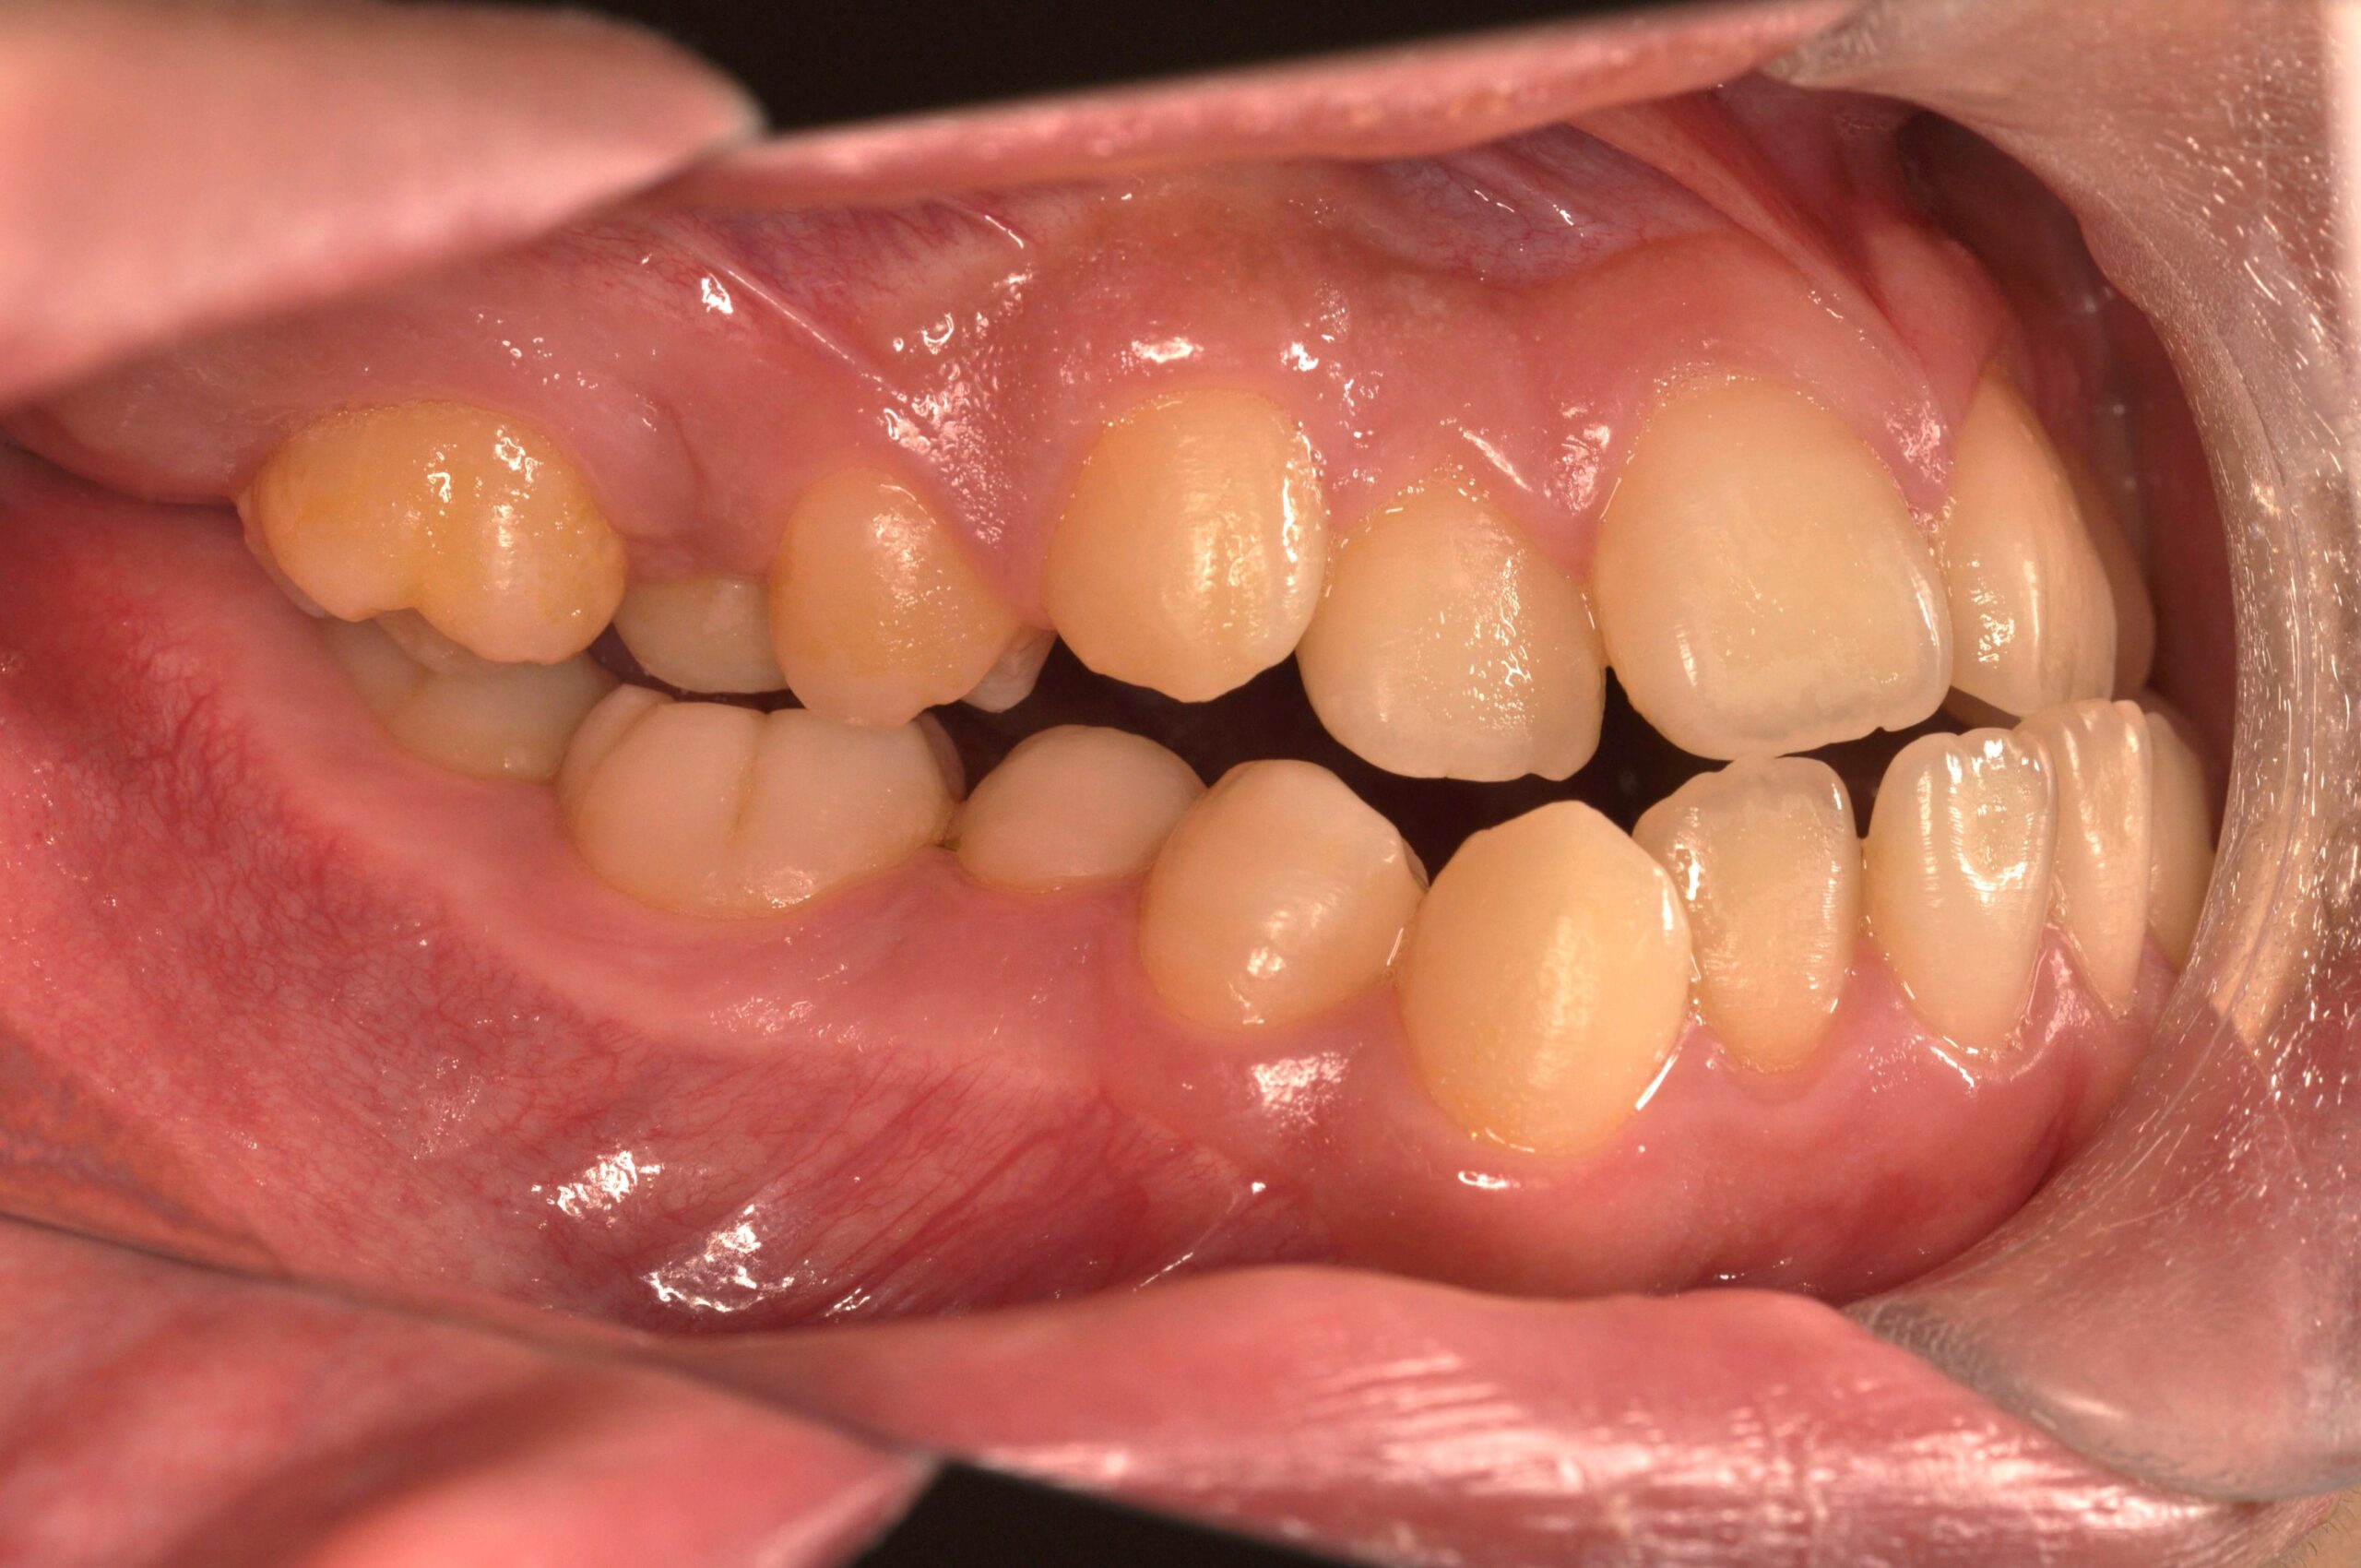

症例情報の閲覧をご希望の方は、画像をタップまたはクリックしてご覧ください。(医療広告ガイドラインに基づき掲載しています)

症例紹介